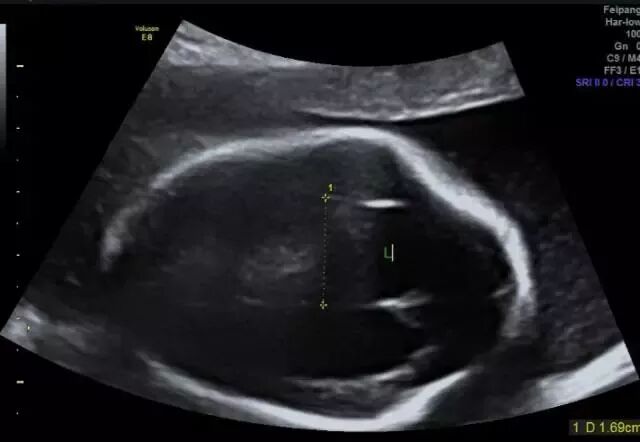

目前检查胎儿是否畸形,国际上最通用也是很安全的方式是超声检查。现在国际上这方面最普遍的仪器就是美国GE集团的GE Voluson E8四维彩超仪器,阳泉华康医院作为阳泉专业妇产医院,率先引进美国GE Voluson E8四维彩超设备,为母婴健康保驾护航。

美国GE Voluson E8对胎儿心脏、唇裂、四肢发育异常、脑膜膨出、脊柱裂、腹壁裂等先天性畸形及发育异常能达到最佳的检测效果,为临床诊断提供准确的科学依据。

胎儿常见畸形检查图

(脊柱裂)